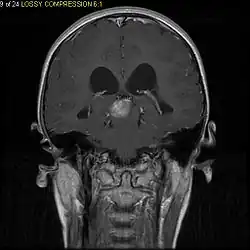

Pilocytic astrocytoma (and its variant pilomyxoid astrocytoma) is a brain tumor that occurs most commonly in children and young adults (in the first 20 years of life). They usually arise in the cerebellum, near the brainstem, in the hypothalamic region, or the optic chiasm, but they may occur in any area where astrocytes are present, including the cerebral hemispheres and the spinal cord. These tumors are usually slow growing and benign, corresponding to WHO malignancy grade 1.[1]

Usually – depending on the interview of the patient and after a clinical exam which includes a neurological exam and an ophthalmological exam – a CT scan and/or an MRI scan will be performed to confirm the presence of a tumor. They are usually easily distinguishable from normal brain structures using these imaging techniques. A special dye may be injected into a vein before these scans to provide contrast and make tumors easier to identify. Pilocytic astrocytomas are typically clearly visible on such scans, but it is often difficult to say based on imaging alone what type of tumor is present.

Pilocytic astrocytomas are often cystic tumors, and, if solid, tend to be well-circumscribed.